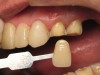

Figure 14. The patient wearing a preview of his potential new smile with a temporary bisacrylic material, Shade A1, based on his mock wax-up. Before polishing and adding glaze, the author performed the additive/reductive method to individualize the original wax-up to better balance any asymmetry.

Figure 14